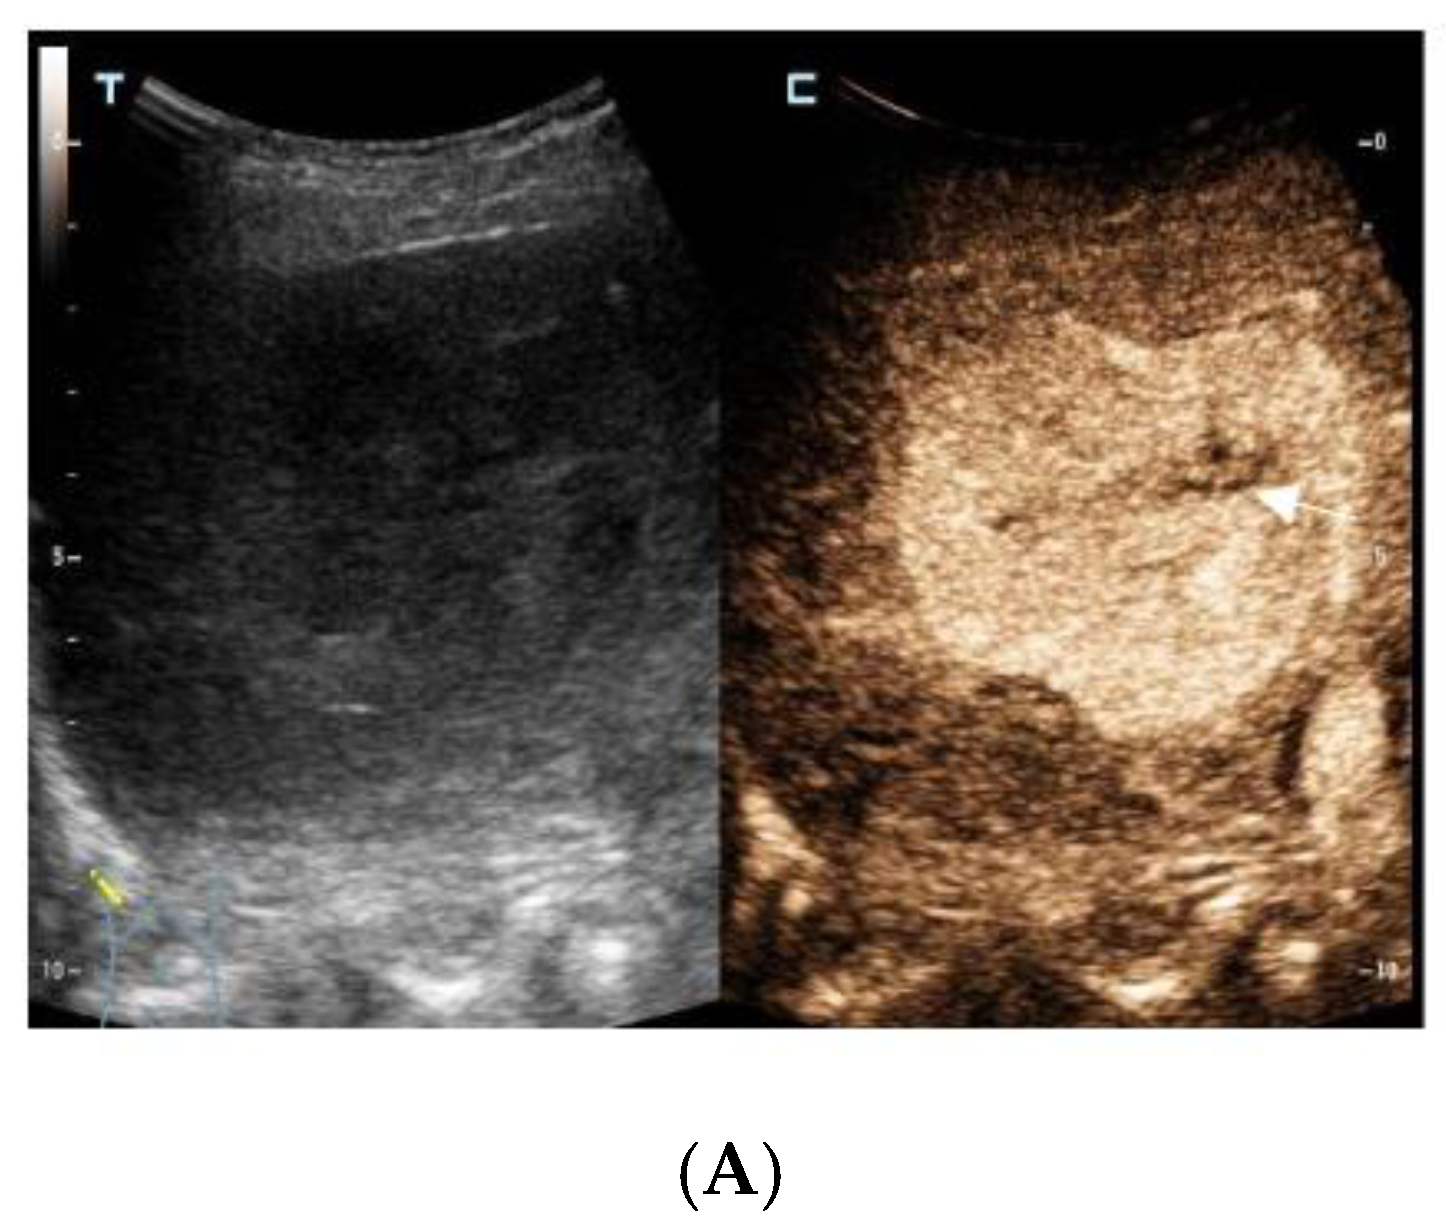

The contrast-enhanced ultrasound images of the hepatic lesion. A 71-year-old man presented at our medical center with intermittent fever in the morning and night for two weeks, accompanied by pain in the back. His body temperature was up to 39 °C, which subsided after anti-inflammatory treatment at the local hospital. He didn’t have a cough, expectoration, chest tightness, or joint pain. The medical history recorded that he had diabetes, hypertension, and suffered tuberculosis ten years ago. Currently, his spot test for mycobacterium tuberculosis (T-Spot) was negative, but his erythrocyte sedimentation rate (ESR) was 72 mm/H (normal range < 28 mm/H) and C-reaction protein (CRP) was 46.4 mg/L (normal range: 0–10 mg/L). Laboratory tests were negative for hepatitis B virus (HBV), hepatitis C virus (HCV), or human immunodeficiency virus (HIV) infection. The serum tumor markers of alpha-fetoprotein (AFP) and CYFRA 21-1 produced negative results, whereas the levels of carcino-embryonic antigen (CEA, 5.9 ng/mL, normal range: 0–5 ng/mL), carbohydrate antigen 199 (CA199, 45.0 U/mL, normal range: 0–34 U/mL), squamous cell carcinoma antigen (SCC, 3.8 ng/mL, normal range: 0–3.0 ng/mL), and neuron specific enolase (NSE, 16.4 ng/mL, normal range: 0–16.3 ng/mL) were slightly higher than the normal range. A computed tomography (CT) scan of the chest showed subcentimeter (2–4 mm) nodules in the lung, which were suspected to be tuberculosis or metastatic tumors. A low-density mass was accidentally observed in the right posterior lobe of the liver. On gray-scale ultrasound, a 65 mm hypoechoic lesion was revealed in segment seven (S7) of the liver with a regular shape and well-defined margin. After injection of SonVue® (Bracco, Milan, Italy), the lesion showed heterogeneous hyperenhancement in the arterial phase (A). During portal venous and late phase, the lesion showed continuous isoenhancement compared with the surrounding liver parenchyma (B,C). It became slightly hypo-enhanced until seven minutes later (D). Unenhanced area was observed during the whole enhancement phase (A–C, arrow). Considering the medical history of fever, diabetes, and absence of HBV infection, the liver nodule was initially diagnosed as hepatapostema.